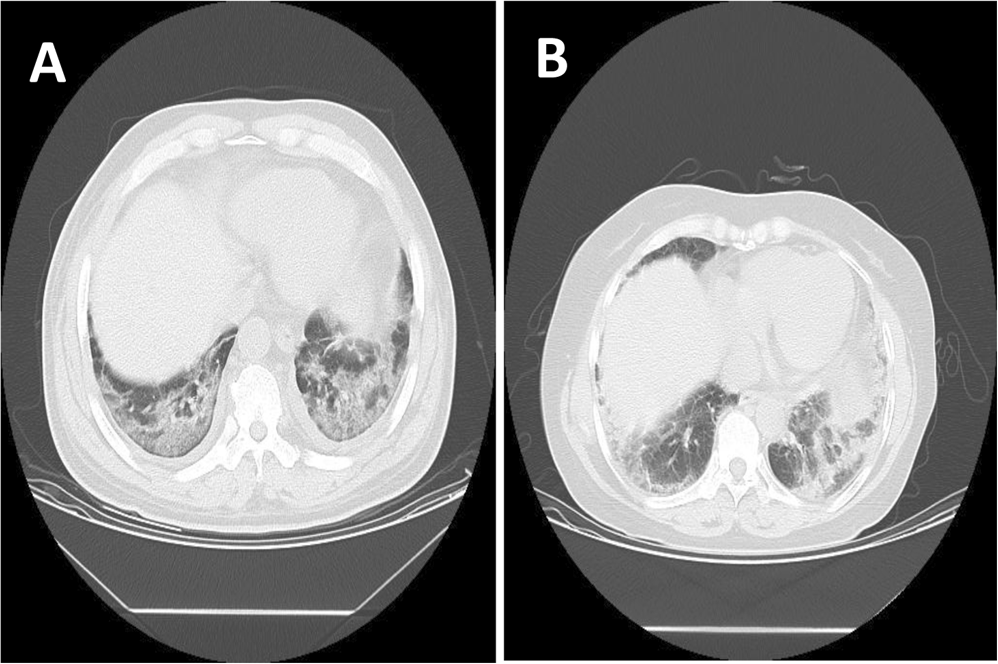

A paraquat poisoning patient (A) and a pneumonia patient (B) who were underwent CT scan.